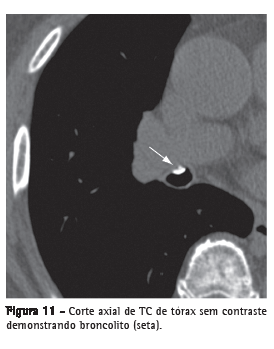

BroncolitoLinfonodo peribrônquico calcificado que erode para o interior do brônquio adjacente, geralmente secundário a infecções por Histoplasma sp. ou Mycobacterium tuberculosis. Na TC, é identificado como um pequeno foco de calcificação dentro da ou adjacente à via aérea, mais frequentemente no brônquio do lobo médio (Figura 11). Distalmente, pode existir impacção de secreções, bronquiectasias ou atelectasia.(24,25)